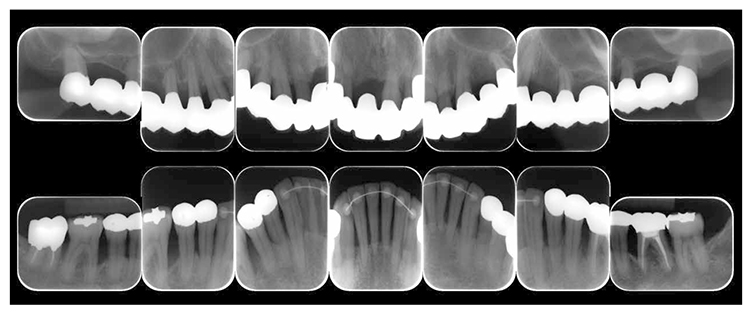

After orthodontic treatment was completed, fabrication of the final prosthesis was started.. Preliminary impression of the maxilla and mandible were taken, anatomic facebow and checkbite were obtained, and prosthetic diagnosis was performed. In the treatment plan before surgery, the first choice for the maxilla was the full mouth bridge that connects all teeth. However, since no parallelism was seen on the anchor teeth, and additionally all teeth were vital teeth, convenient pulpectomy was sought as a possibility. Additionally, in designing treatment for patients with severe periodontitis, to disperse the occlusal load to the entire jaw, which was most important, semi-fixed multi-tooth prosthetic using key and keyway attachment was designed for final prosthetic in this case. After taking parallelism of anchor teeth into consideration, multi-tooth models with attachments were designed for 13 and 14, and for 22 and 23. After deciding on the shape of prosthetics, anchor teeth were formed, impression was taken, and subsequently final confirmation was made on accurate fit with coping trial. After final prosthetic treatment on the maxilla, prosthetics were placed on the mandible starting with 47. Since metal crowns were placed on both 47 and 36, onlay-type metal crowns were placed on 44, 45, 34 and 35 for occlusal support. After completion of prosthetic treatment on all teeth, confirmation was made with an occlusal force tester (Dental Prescale®,GC, Tokyo) that occlusal force was equally distributed across the entire jaw. Additionally, nighttime bruxism was addressed by producing and applying nightguards since the patient had the habit of clenching.

7) Reevaluation testing (December 2003)

At the reevaluation examination after treatment to restore oral function, the color of gingiva was pink, and with prosthetics, intraoral harmony was replicated esthetically and functionally. (Fig.6a). The average PD across the entire jaw was 2.1mm, maximum PD was 4.0mm, the ratio of PD of 3mm or below was 99.3%, no BOP was found and the condition of the periodontal tissue was stable (Fig.6b). In the X-ray, continuity of the alveolar hard line was replicated and the sequence of bone trabeculae was normal, and therefore, the patient transitioned to the SPT phase (Fig.6c).

Fig 6c

(Fig.6c) Digital X-ray 14 after completion of restoration of oral function (April 2013)